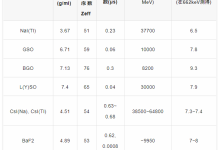

光子计数探测器由碲镉(CdTe)、碲锌镉(CZT)或硅(Si)等半导体制成。由于原子序数较高,碲化镉和碲锌镉层可以相对较薄(1.4-2mm),但仍能提供较高的X射线吸收率。而由硅制成的光子计数探测器则需要更厚(30-60mm)才能充分吸收X射线。根据目前的文献,所有临床前或临床使用的PCD-CT都配备了碲化镉或碲锌镉探测器。图1显示了基于碲化镉或碲锌镉的PCD的结构示意图。在半导体层的上侧是一个大面积的阴极电极,在下侧为像素化阳极电极。在阴极和单个阳极之间施加800-1000 V的高压,可产生强大的电场。入射的X射线被半导体吸收,产生的电荷(电子-空穴对)在电场中分离。电子移动到阳极,在那里产生持续时间约为1 ns(109 s)的短电流脉冲,通过电子脉冲整形电路转换成半宽(FWHM)为10-15 ns的电压脉冲。电压脉冲的脉冲高度与X射线的吸收能量E成正比。一旦脉冲超过阈值TL,即吸收能量(通常为20-25 keV),读出电子装置就会对其进行计数。在技术实现中,使用了一个脉冲高度比较器电路,其中输入了与阈值能量相对应的电压,参见图1。探测器信号相当于在投影测量时间内记录的所有脉冲的总和。